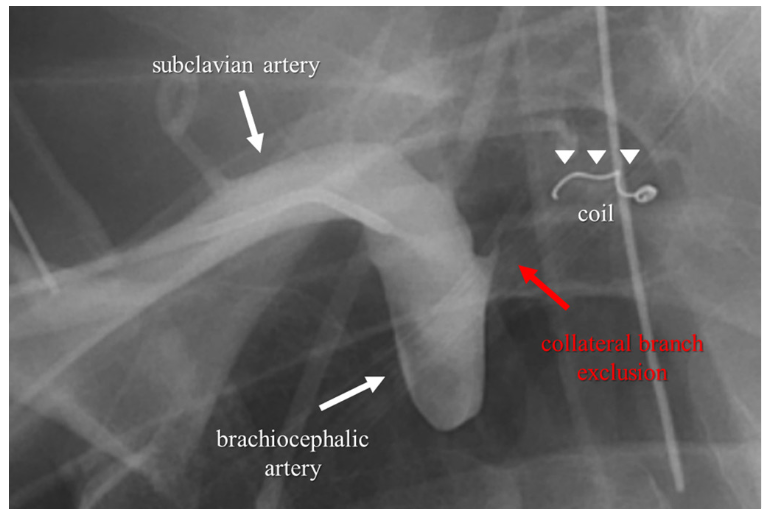

Coil embolization of the collateral pathway (arrow) from the Coil Embolization En Espanol en este artículo se presentan dos casos de embolia pulmonar aguda no trombótica asociada a complicación de embolización. según los resultados a medio plazo, la embolización con coil es un tratamiento endovascular factible para los. This procedure is also called. se utiliza para la embolización arterial y venosa en la vasculatura periférica. Es un procedimiento para tratar. Coil Embolization En Espanol.